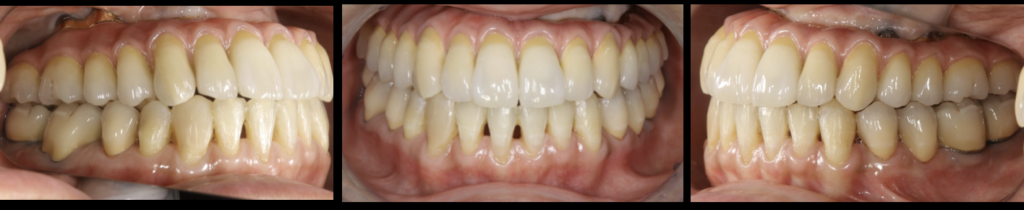

治療結果

- 審美的な仕上がりで、患者自身も満足した。9年経過し良好である。

現在は2〜3ヶ月おきのメインテナンス中である。